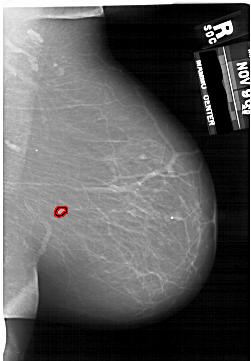

A_1623_1.RIGHT_CC

RIGHT_CC LINES 6466 PIXELS_PER_LINE 4051 BITS_PER_PIXEL 12 RESOLUTION 43.5 OVERLAY

FILE: A_1623_1.RIGHT_CC.OVERLAY

TOTAL_ABNORMALITIES 1

ABNORMALITY 1

LESION_TYPE MASS SHAPE IRREGULAR MARGINS ILL_DEFINED

ASSESSMENT 4

SUBTLETY 2

PATHOLOGY MALIGNANT

TOTAL_OUTLINES 1

BOUNDARY